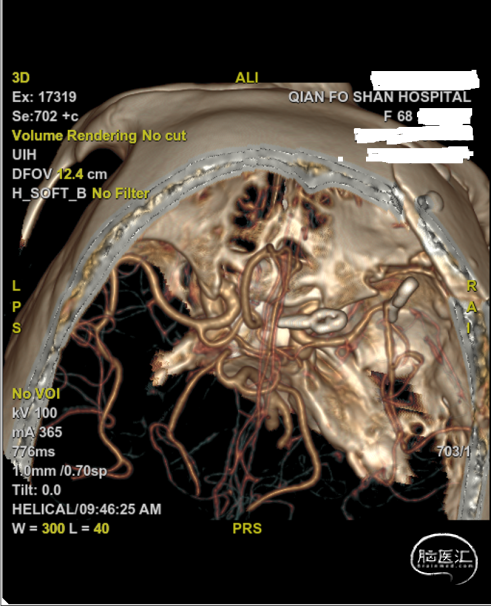

入院后行DSA检查,显示右侧颈内C6-7段动脉瘤右侧大脑中动脉M1分叉动脉瘤。

C6-7段动脉瘤位于颈内动脉上壁,指向内上方,考虑血泡样动脉瘤,结合蛛血位置,及动脉瘤形态、大小,考虑颈内动脉血泡为责任动脉瘤。